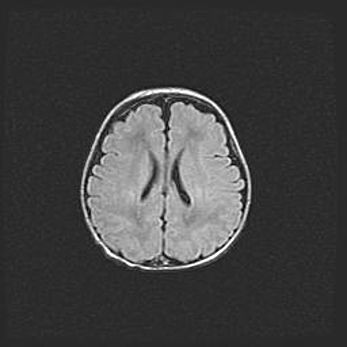

Наружная гидроцефалия с возможной атрофией височных областей.

Возраст: 28 дней

Вес: 3670 г

Пол: мужской

Окружность головы: 38 см

Срок гестации: 40 недель

Гидроцефалия головного мозга у новорожденных – это заболевание, которое характеризуется скоплением избыточного количества спинномозговой жидкости в желудочковой системе головного мозга в результате затруднения её перемещения от места выработки к месту поглощения в кровеносную систему или вследствие нарушения абсорбции. При открытой наружной форме гидроцефалии у новорожденных расширяются и переполняются субарахноидные пространства.

При нормотензивных  формах,  которые,  как  правило,  являются  следствием  перенесенных ишемических  повреждений  паренхимы  мозга,  возможно  сочетание микроцефалии  с нормотензивной гидроцефалией. В основе данных изменений лежит атрофия больших полушарий с преимущественной  локализацией  в  лобно-височных  областях.